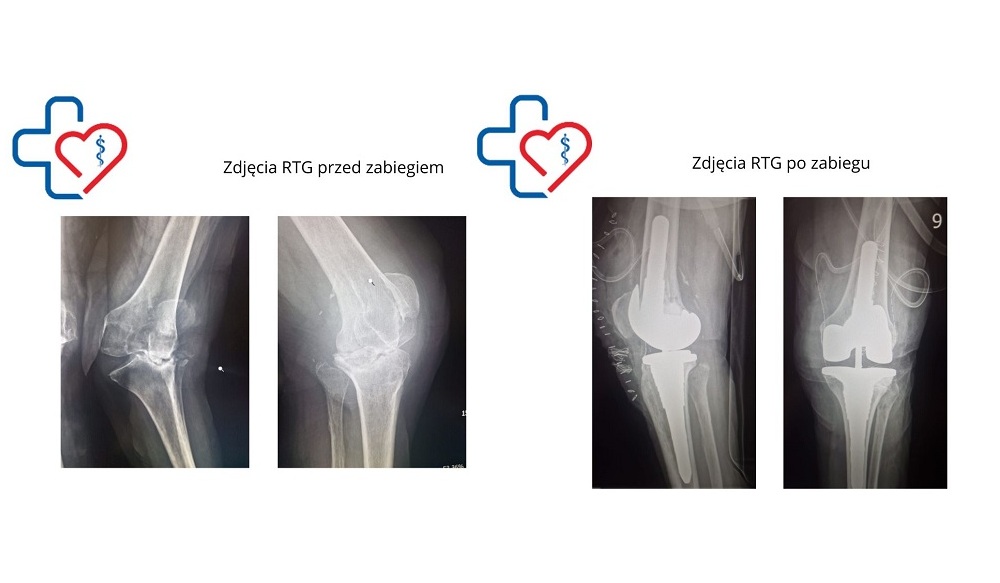

Lekarz wyjaśnia, że operacja była wyjątkowo skomplikowana ze względu na znaczne zniekształcenie kolana i jego niestabilność. - To była pierwotna endoproteza, ale pacjentka miała dużą deformację koślawą, czyli tzw. „iksy”. Kolano było niestabilne, a więzadło przyśrodkowe – które powinno je stabilizować – nie spełniało swojej roli. W takim przypadku klasyczna endoproteza nie zdałaby egzaminu, szybko by się obluzowała i konieczne byłyby kolejne operacje, co w tym wieku wiązałoby się z dużym ryzykiem - tłumaczy Wojciech Stochmiałek.

Dlatego zespół ortopedów sięgnął po specjalną protezę częściowo związaną, która jednocześnie zastępuje uszkodzone więzadła i uzupełnia ubytki kostne. Implant został zakotwiczony głęboko w kości udowej i piszczelowej. - Zabieg był technicznie wymagający, konieczne było uwolnienie stawu, aby mógł w pełni się zginać i prostować - dodaje lekarz.

Operacja trwała około dwóch godzin i przebiegła zgodnie z planem. Zespół miał przygotowane alternatywne rozwiązania, które mogłyby zostać wykorzystane w razie komplikacji. Ostatecznie udało się wszczepić protezę z zestawu rewizyjnego – rozwiązanie rzadko stosowane przy pierwszych operacjach, ale w tym przypadku konieczne.

- Zabieg zakończył się sukcesem. Już czwartego dnia po operacji pacjentka opuściła szpital. Bardzo szybko odzyskała sprawność, a kolano pracuje prawidłowo – jest stabilne, nie ucieka ani do boków, ani do przodu czy tyłu. Zakres ruchu wynosi od 0 do 90 stopni, co w tym wieku jest świetnym wynikiem - podsumowuje specjalista.